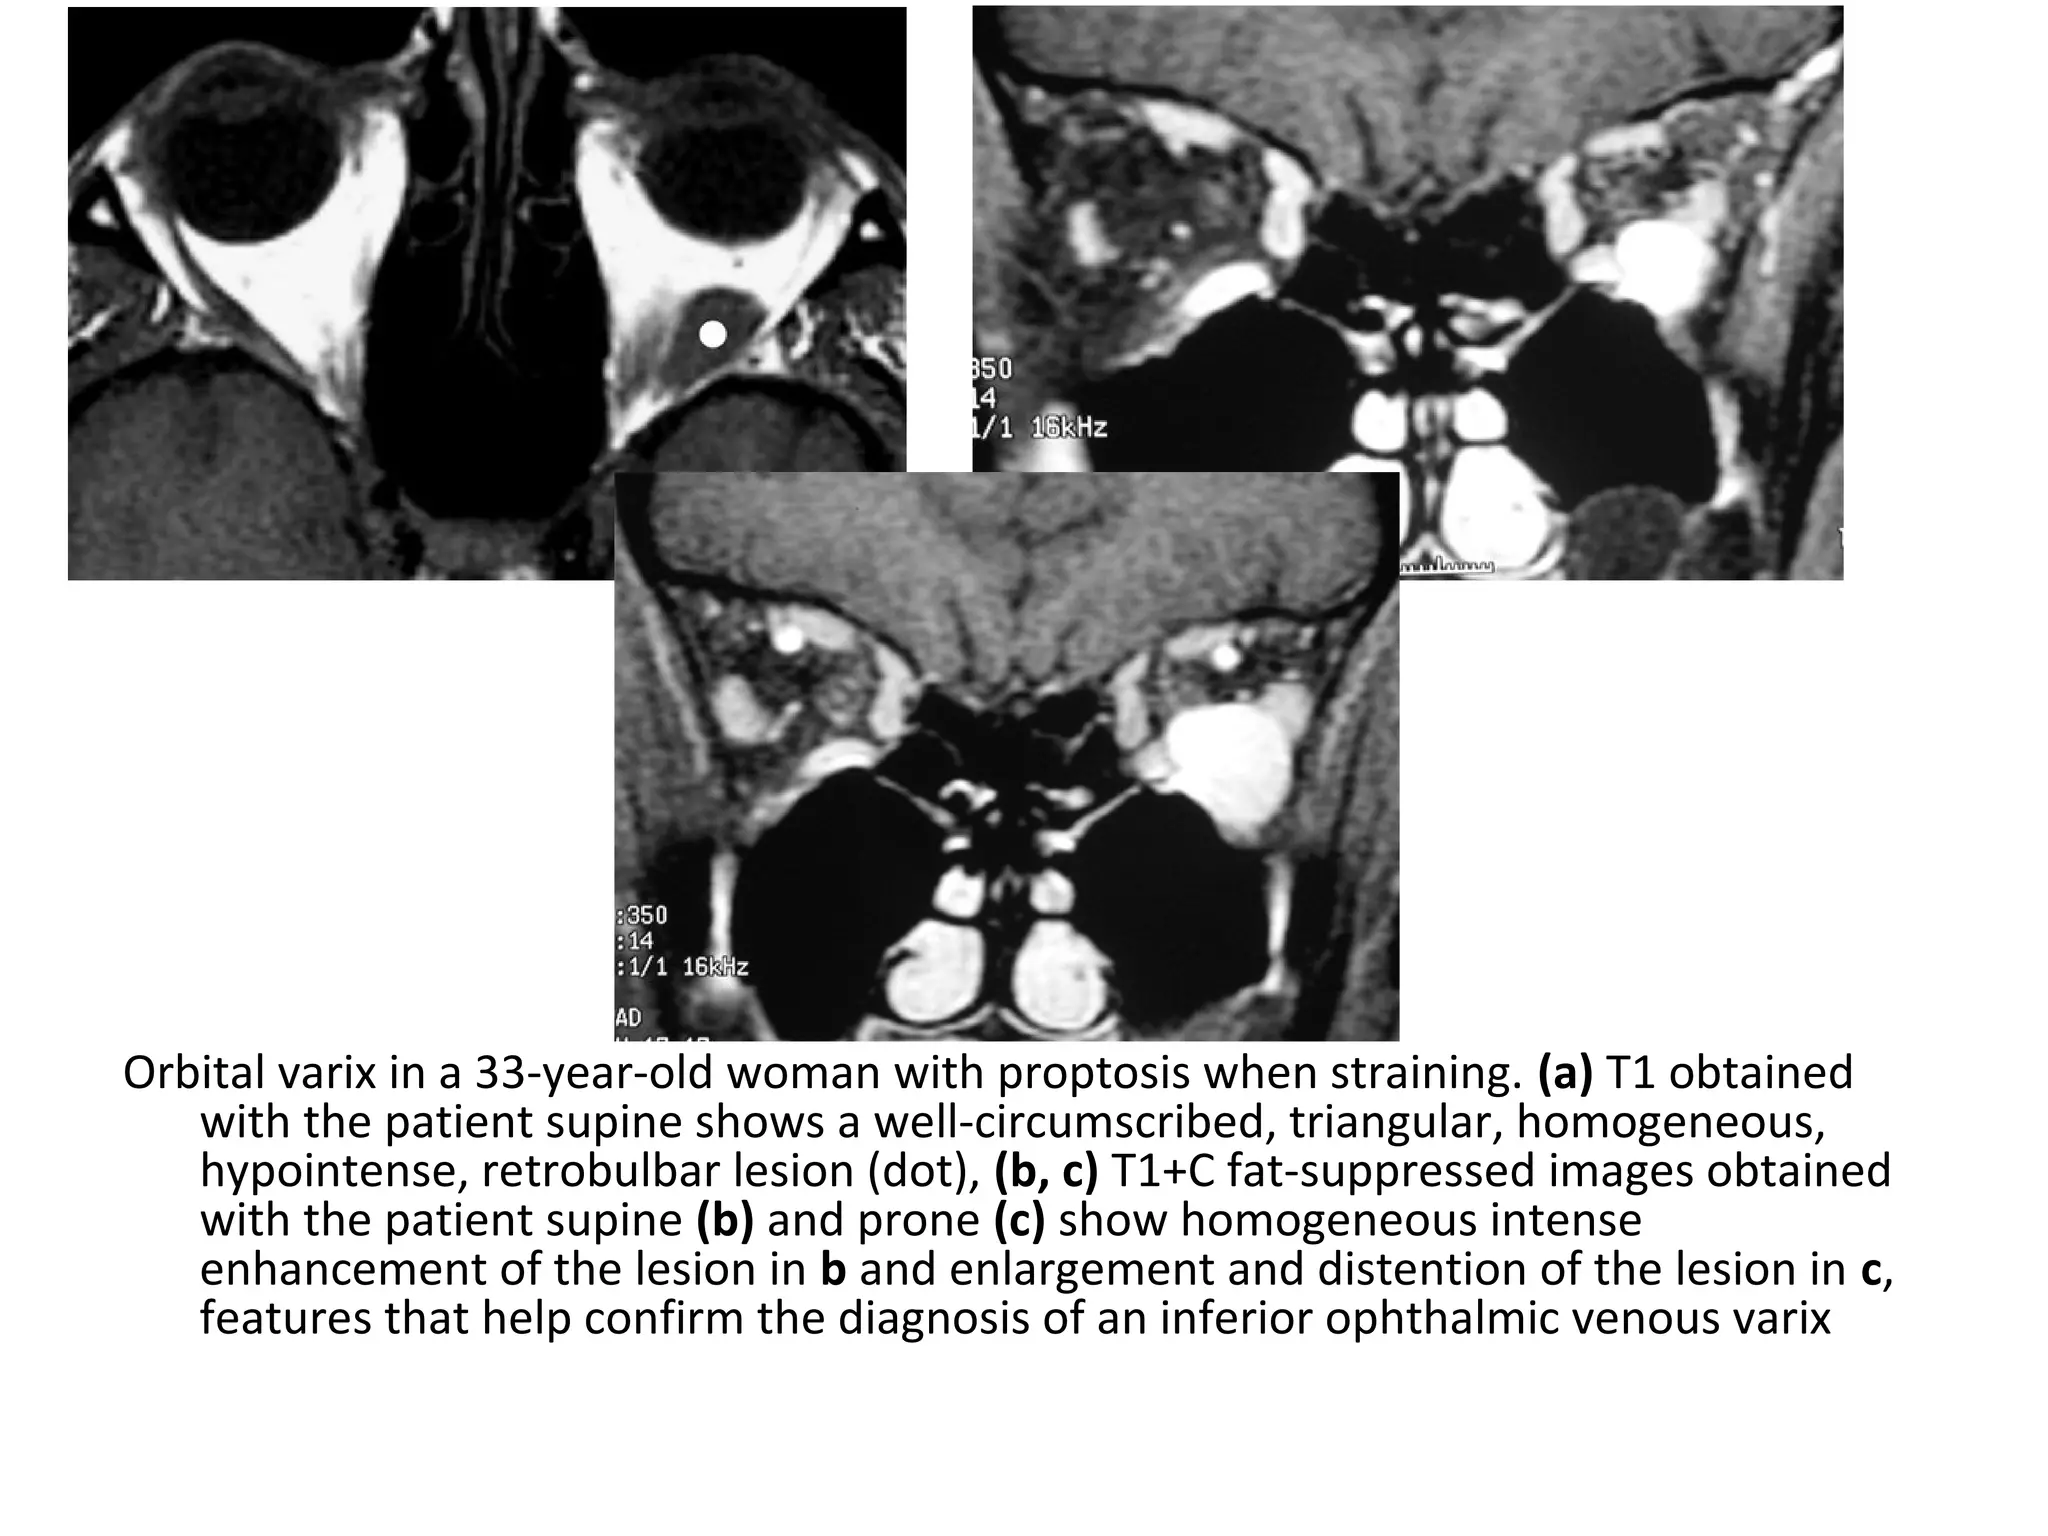

Orbital varix in a 33-year-old woman with proptosis when straining. (a) T1 obtained

with the patient supine shows a well-circumscribed, triangular, homogeneous,

hypointense, retrobulbar lesion (dot), (b, c) T1+C fat-suppressed images obtained

with the patient supine (b) and prone (c) show homogeneous intense

enhancement of the lesion in b and enlargement and distention of the lesion in c,

features that help confirm the diagnosis of an inferior ophthalmic venous varix